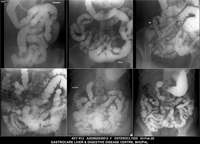

Section: ENTEROCLYSIS

Total: 205 Cases